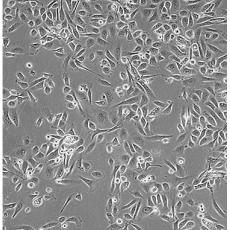

PC-3(PC 3)

產品名稱 PC-3(PC 3)

中文名稱 人前列腺癌細胞

組織來源 前列腺癌;骨髓轉移;男性

細胞種屬 Homo sapiens, human

生長特性 adherent

培養基 Ham's F-12K+10% FBS+1% P/S

形態特征 epithelial

傳代方法 1:3-1:6

細胞描述 PC-3源于一位62歲白人男性IV級前列腺腺癌患者的骨轉移灶;有低水平的酸性磷酸酶活性和5-α-睪酮還原酶活性。